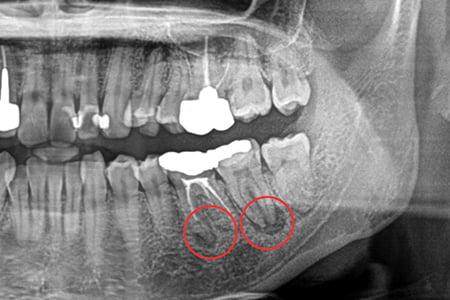

治療例2

| 症状 | 左下奥歯が噛むと違和感がある |

|---|---|

| 治療方針 | 歯根嚢胞を認め歯が保存可能か分析。保存可能であれば根管充填及びファイバーコア、補綴修復を行う |

| 治療期間 | 1年9カ月 |

| 治療費用(税込) | ¥666,600 ※2歯分 |